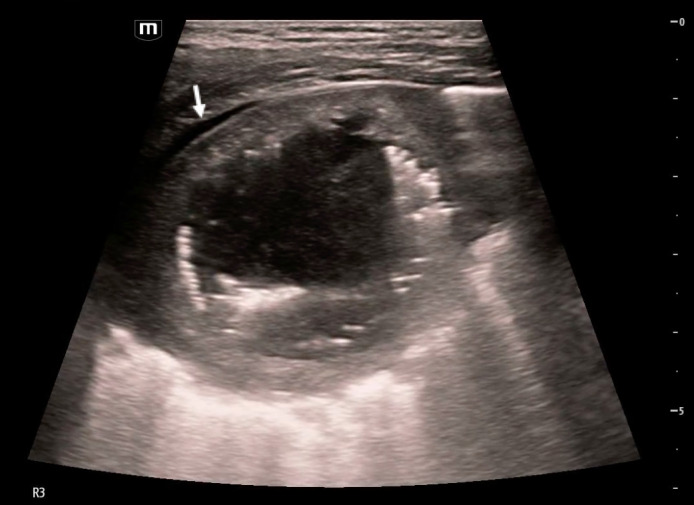

Application of ultrasound to evaluate pediatric respiratory disease in the emergency department setting is rapidly growing, particularly as we often weigh the risks of exposure to radiation with other readily available imaging modalities in the acute care setting. In this case report, we describe how point of care ultrasound (POCUS) was utilized by emergency providers to characterize a lung abscess diagnosed in a pediatric patient. We also compare the ultrasound findings to other imaging studies.

Abstract Image